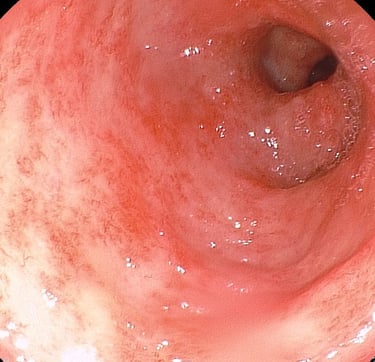

Pólipo de colon

Resección de polipos del colon

(polipectomía)